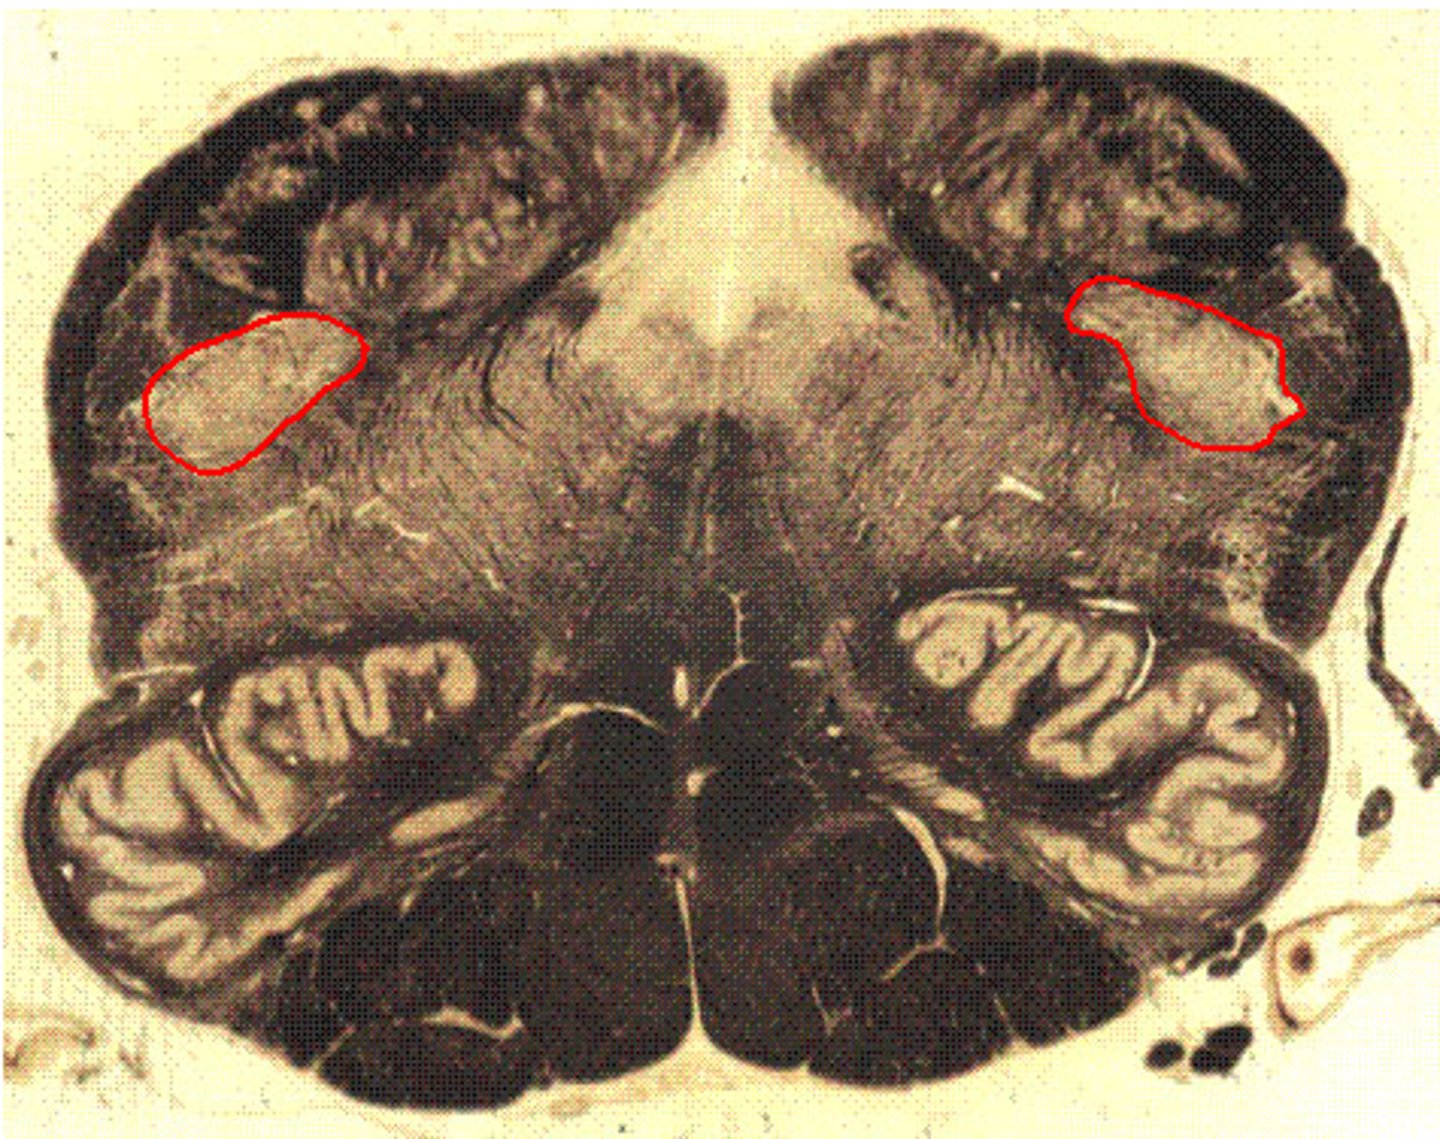

Medulla Pyramidal Decussation

Fasciculus Cuneatus

Fasciculus Gracilis

Nucleus Cuneatus

Nucleus Gracilis

Spinal Trigeminal Tract

Spinal Trigeminal Nucleus

Pyramid

Pyramidal Decussation